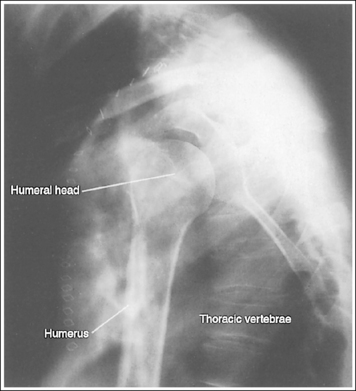

See Figures 4-86 and 4-87 and Box 4-22.

Scatter radiation is controlled. Image density is uniform across the humerus.

The humerus is in an AP projection. The medial and lateral humeral epicondyles are demonstrated in profile, and the radial head and tuberosity are superimposed over the lateral aspect of the proximal ulna by approximately 0.25 inch (0.6 cm). The greater tubercle is demonstrated in profile laterally, the humeral head is demonstrated medially in profile, and the vertical cortical margin of the lesser tubercle is visible approximately halfway between the greater tubercle and the humeral head.

• An AP projection is obtained by placing the patient in a supine or upright AP projection, with the affected arm extended. Supinate the hand and externally rotate the elbow until an imaginary line drawn between the palpable humeral epicondyles is aligned parallel with the IR (Figure 4-88). This positioning places the proximal radius anterior to the ulna, causing the radial head and tuberosity to be superimposed over the lateral ulna by approximately 0.25 inch (0.6 cm), and places the greater tuberosity in profile.

• Detecting humeral rotation. Rotation of the humerus is a result of poor humeral epicondyle positioning. When the humeral epicondyles and the greater tuberosity are not demonstrated in profile, measure the amount of radial head and tuberosity superimposition of the ulna to determine how the patient should be repositioned. If less than 0.25 inch (0.6 cm) of the radial head and tuberosity are superimposed over the ulna, the elbow and humerus have been excessively externally rotated (see Image 100). If more than 0.25 inch (0.6 cm) of the radial head and tubercle are superimposed over the ulna, the elbow and humerus have been internally rotated (see Image 101).